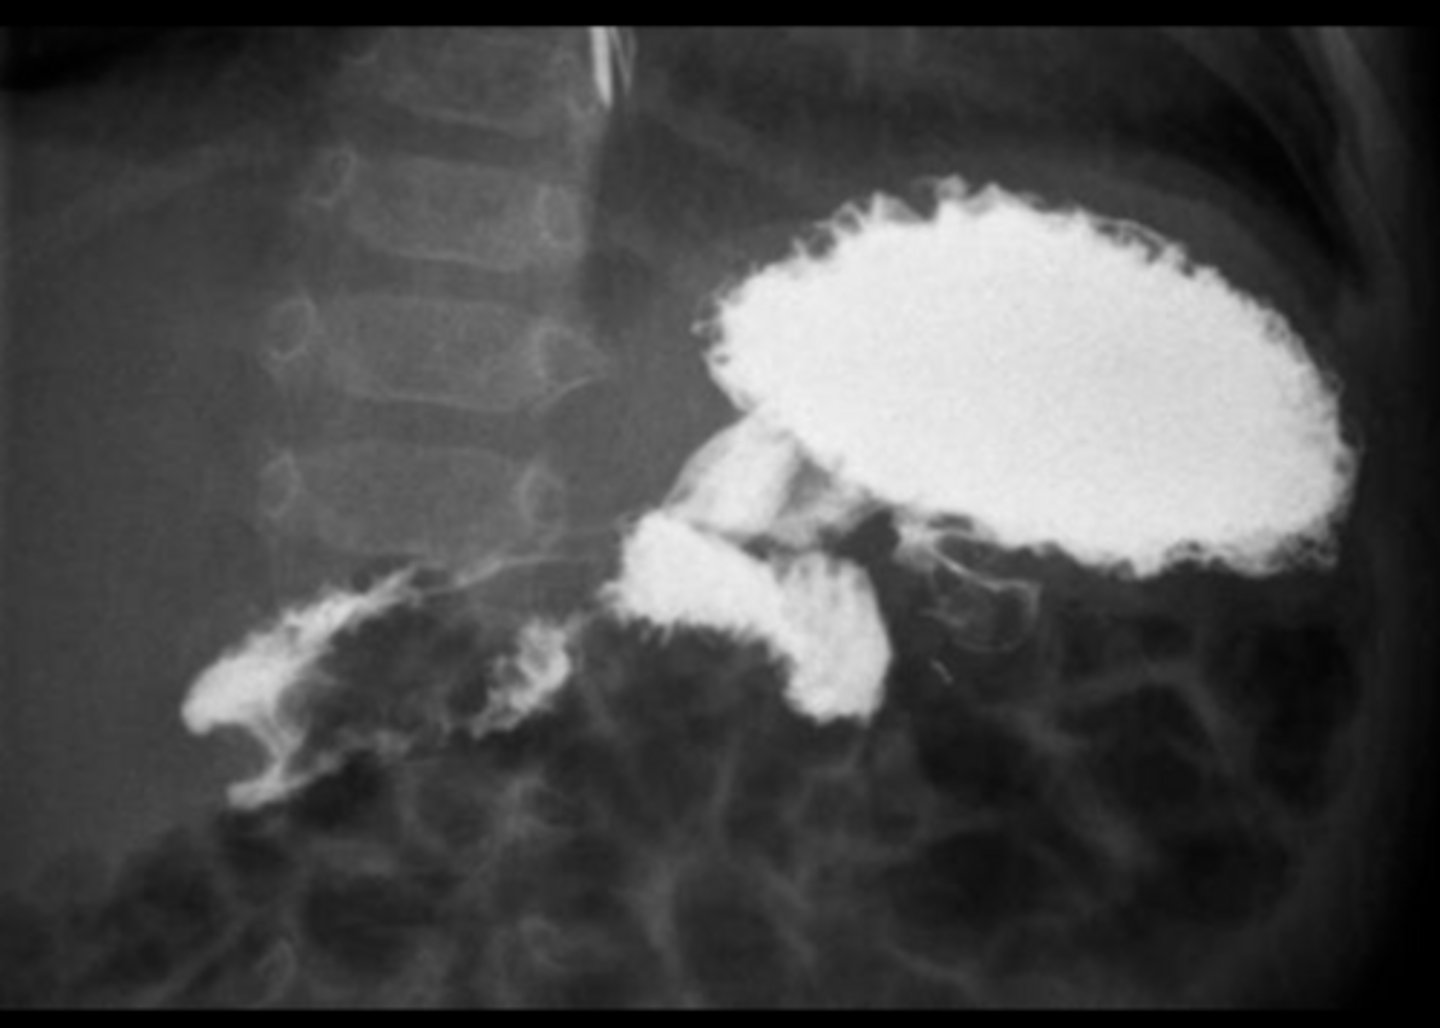

A - Transverse colon

B - Sigmoid colon

C - Cecum/ascending colon/iliocecal junction

pt is on their side due to seeing white fluid and haustra

Label the radiograph

How can patient position on CT be determined using fluid and air distribution?

Fluid moves to the dependent (lowest) side, while air rises to the non-dependent (highest) side due to gravity

Where do fluid and air collect on CT when a patient is supine?

Fluid collects posteriorly (toward the back) and air collects anteriorly.

Where do fluid and air collect on CT when a patient is prone?

Fluid collects anteriorly, while air shifts posteriorly.

How do fluid and air distribute in a side-lying (lateral decubitus) CT?

Fluid settles on the down side, and air rises to the up side.